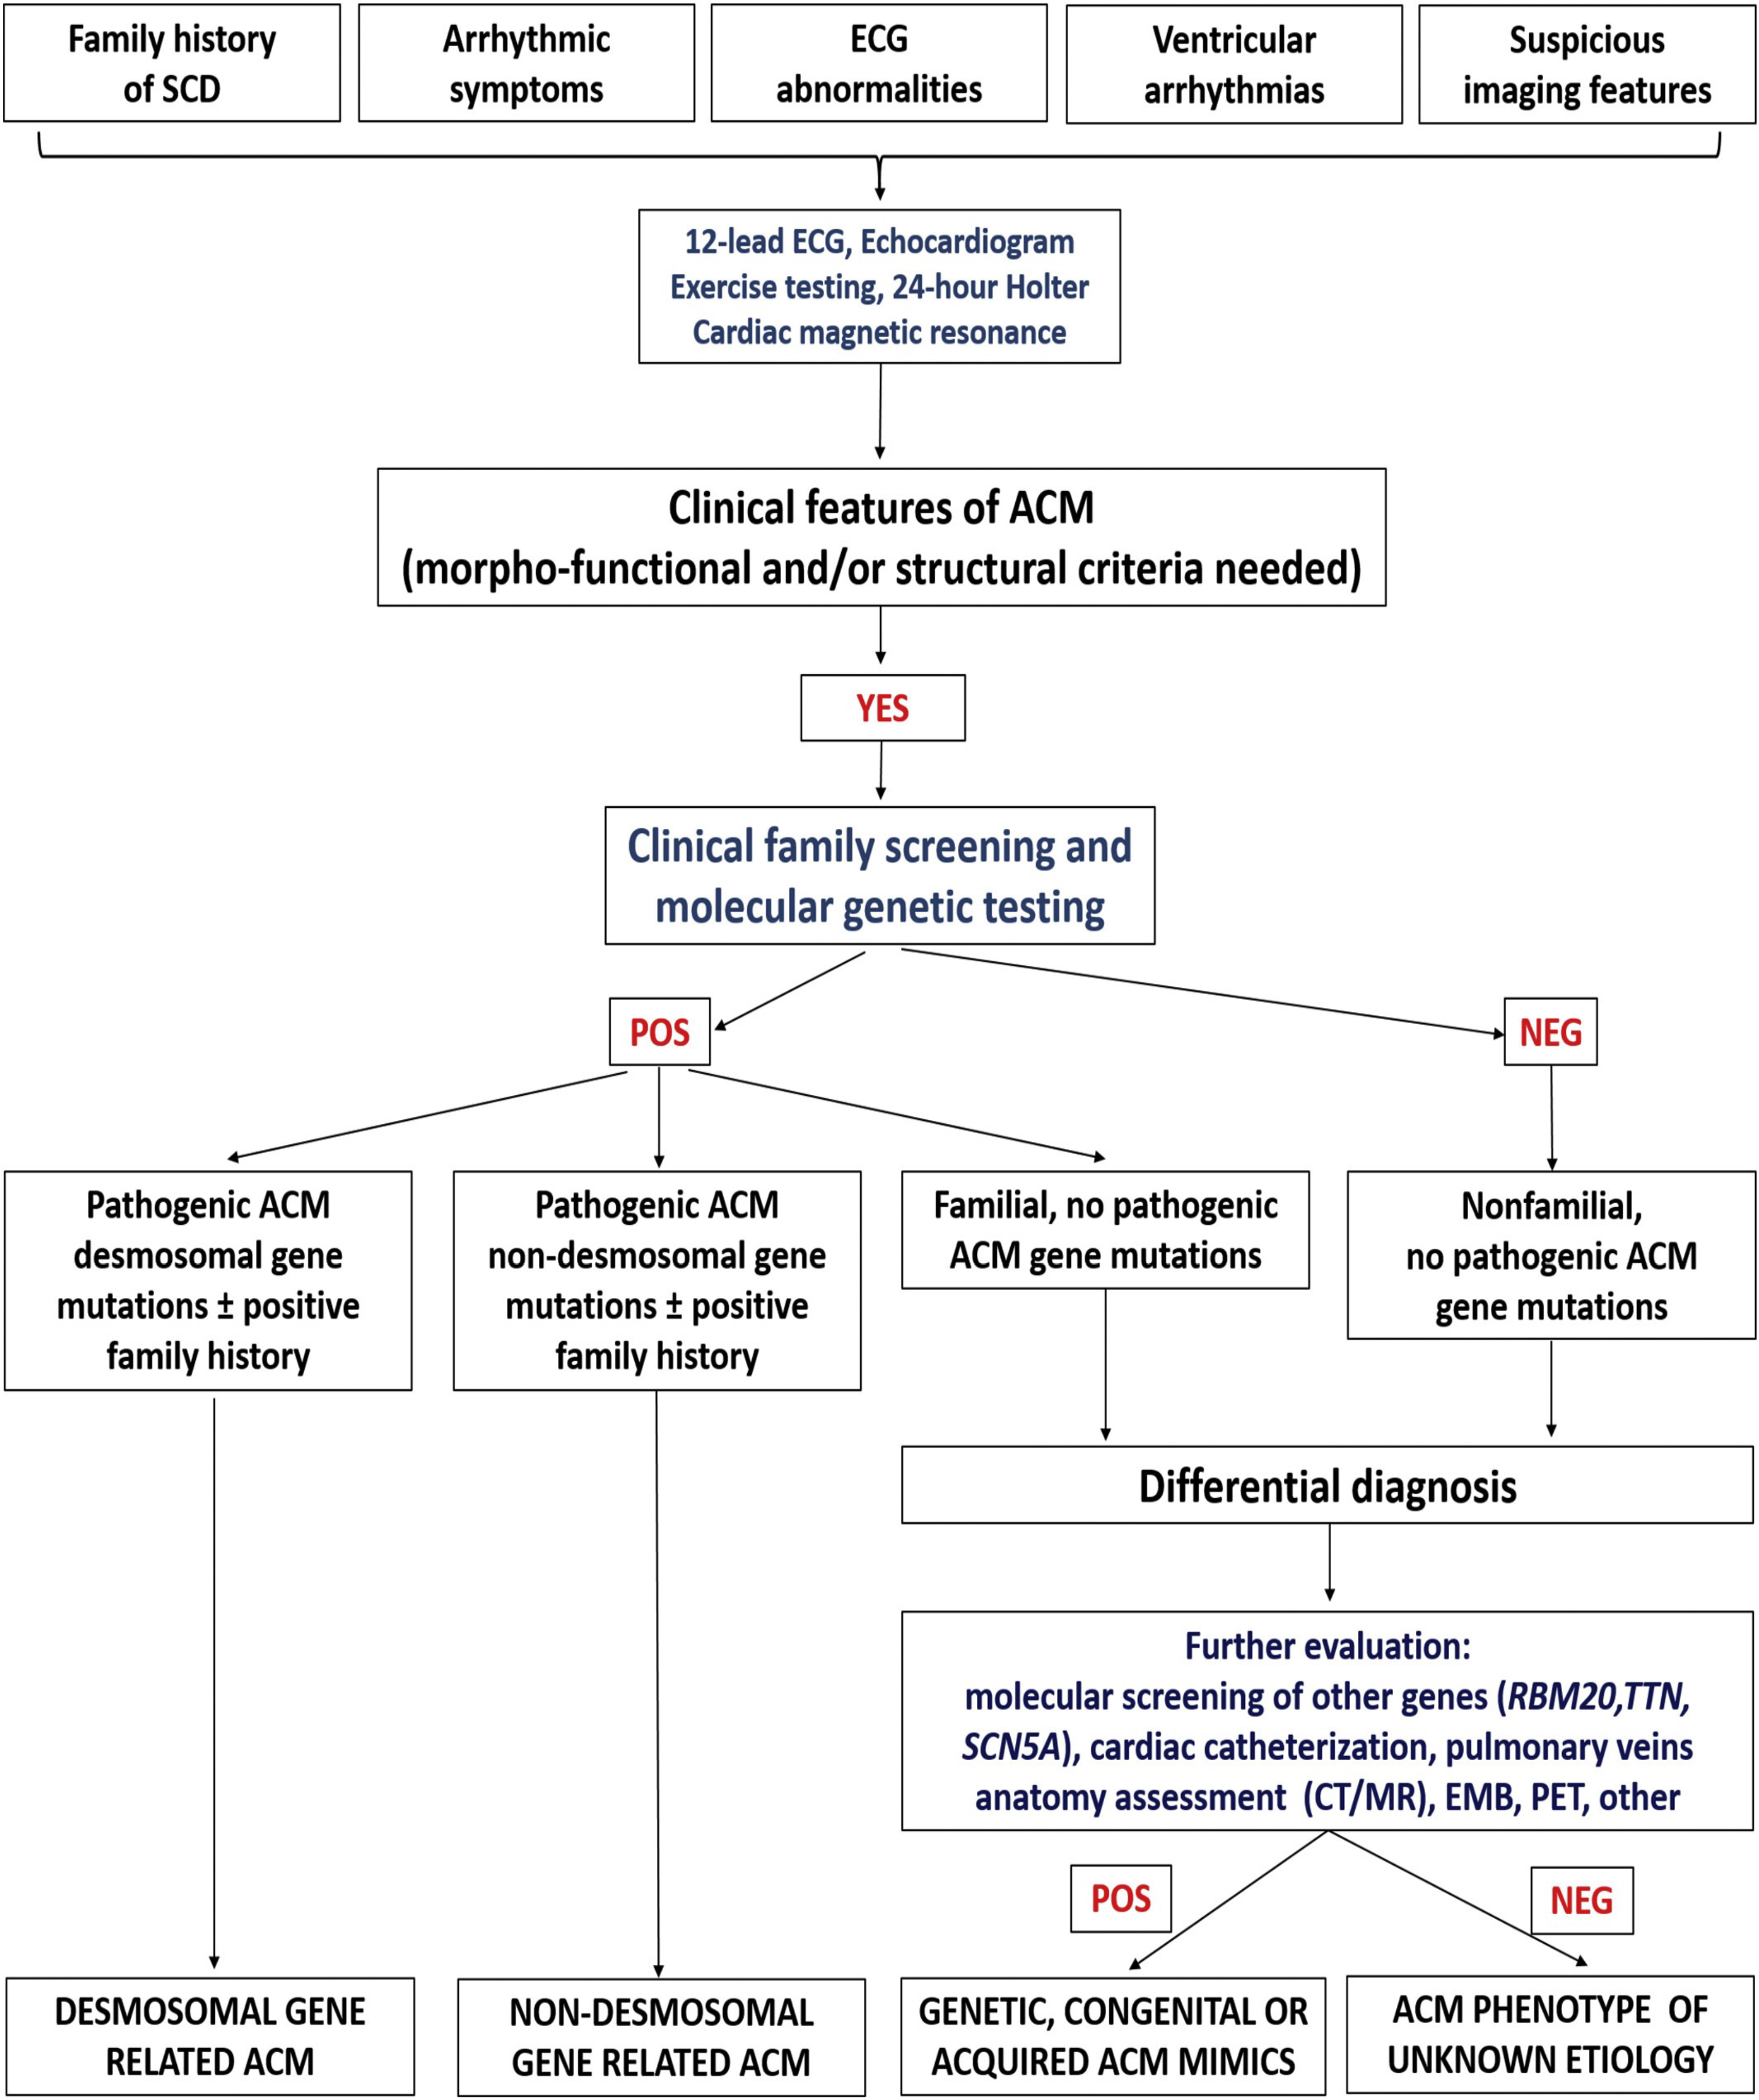

Once the diagnosis is reached, genetic testing and cascade family screening allow to classify the etiology of the disease into four categories: due to desmosomal gene mutation, due to non-desmomal gene mutation, familial but gene-elusive and non-genetic/non-familial. In this last case differential diagnosis with disease phenocopies must be considered, such as cardiac sarcoid (Fig. 2, Ref. [19]).

Fig. 2.

Fig. 2.Flow-chart for etiology assessment of ACM. After the diagnosis is reached in a proband, cascade family screening and molecular genetic testing may allow to identify patients with identified gene mutation in a desmosomal or non-desmosomal gene. In patients with negative genetic testing, cascade family screening may allow to identify other affected family members: in this case, the diagnosis is a familial disease with still unknown genetic basis (so-called “gene elusive”). In case both genetic testing and family screening are negative, further testing may be performed to exclude phenocopies such as congenital heart disease or myocarditis. Adapted from Corrado et al. [19].

After the clinical diagnosis of ACM and the definition of the specific phenotype, the third step is to define the aetiology of ACM and to exclude phenocopies. This purpose can be reached thanks to molecular genetic testing and cascade family screening. Indeed, ACM is generally transmitted as an autosomal dominant trait, with variable expressivity and incomplete penetrance. So, the molecular genetic test can identify either desmosomal or non-desmosomal gene defects causing ACM.

In case of a negative molecular genetic testing but positive clinical family screening, ACM is defined familial but “gene elusive”. Also in this case, the presence of affected relatives allows to rule out non-hereditary conditions mimicking ACM.

If both the genetic testing and the cascade clinical family screening for ACM are negative, it is essential to perform further evaluations in order to exclude mimics, both acquired (sarcoidosis, DCM, pulmonary artery hypertension, myocarditis, Chagas disease) and congenital (left-to right shunt or Ebstein anomaly) phenocopies.